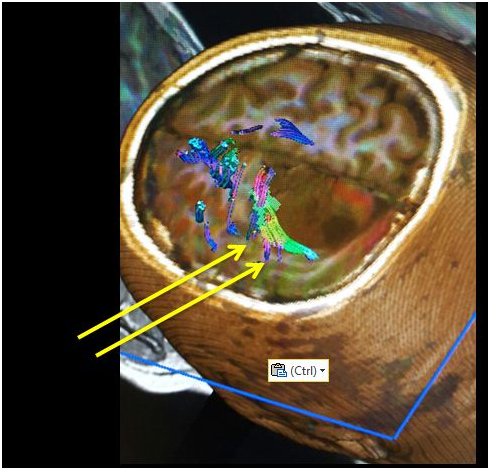

Figure 3 DTI image shows displacement of the cortico spinal tract (arrows).